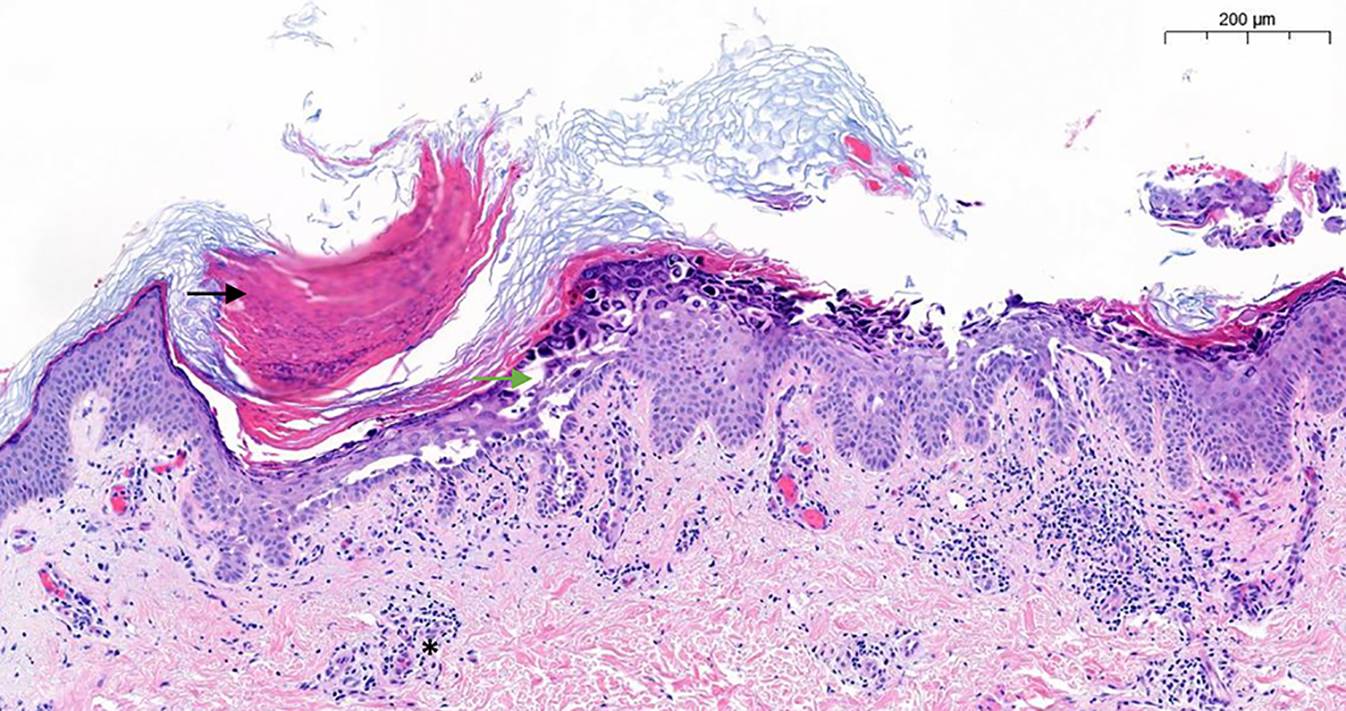

Die Biopsie einer MD-Läsion zeigt klassischerweise das Bild einer akantholytischen Dermatose (Abb. 3). Es können eine Hyperparakeratose und fokale Papillomatose mit suprabasaler Akantholyse, Dyskeratose und das Vorhandensein von runden Körpern sowie Körnern in den Akantholysezonen beobachtet werden [11]. Bei der Untersuchung der Dermis ist ein oberflächliches perivaskuläres lymphozytäres Infiltrat erkennbar.

Abb. 3

Histologische Färbung mit Hämatoxylin und Eosin. Schwarzer Pfeil fokale Hyperkeratose, grüner Pfeil suprabasale Akantholyse und Dyskeratose, Stern Lymphozyteninfiltrat